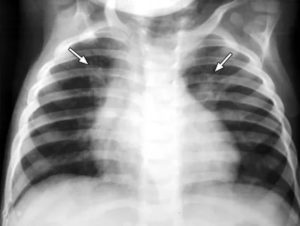

рентгенограмма левосторонней прикорневой пневмонии. Стрелками обозначена деформация легочного рисунка и отсутствие структуры корня (а). Через 2 месяца после пневмонии на фоне воспаления образовались фиброзные тяжи — карнификация (б)

Пневмония на рентгенограмме у пациентов детского возраста не имеет выраженных отличий от взрослых, патология также характеризуется очагами просветления и затемнения. У детей в воспалительный процесс вовлекаются нижние отделы лёгких.

Рентгенография показывает следующее:

- очаговые затемнения диаметром 1-2 мм;

- увеличение внутригрудных лимфоузлов;

- деформация и усиление лёгочно-сосудистого рисунка;

- повышенная плотность затемнения (запущенная патология);

- в области патологического очага изменяется структура и размер лёгочного корня.

Хоть общая картина детского рентгена не различается от взрослого, некоторая разница имеется. Первое — повышенная реактивность функций иммунной системы.

Поэтому даже незначительный инфильтрат способен спровоцировать воспалительную реакцию на обеих долях лёгкого.

При постановке диагноза ребёнку можно ошибиться, что связано с небольшим объёмом лёгочной ткани и повышенным присутствием лёгочного рисунка.